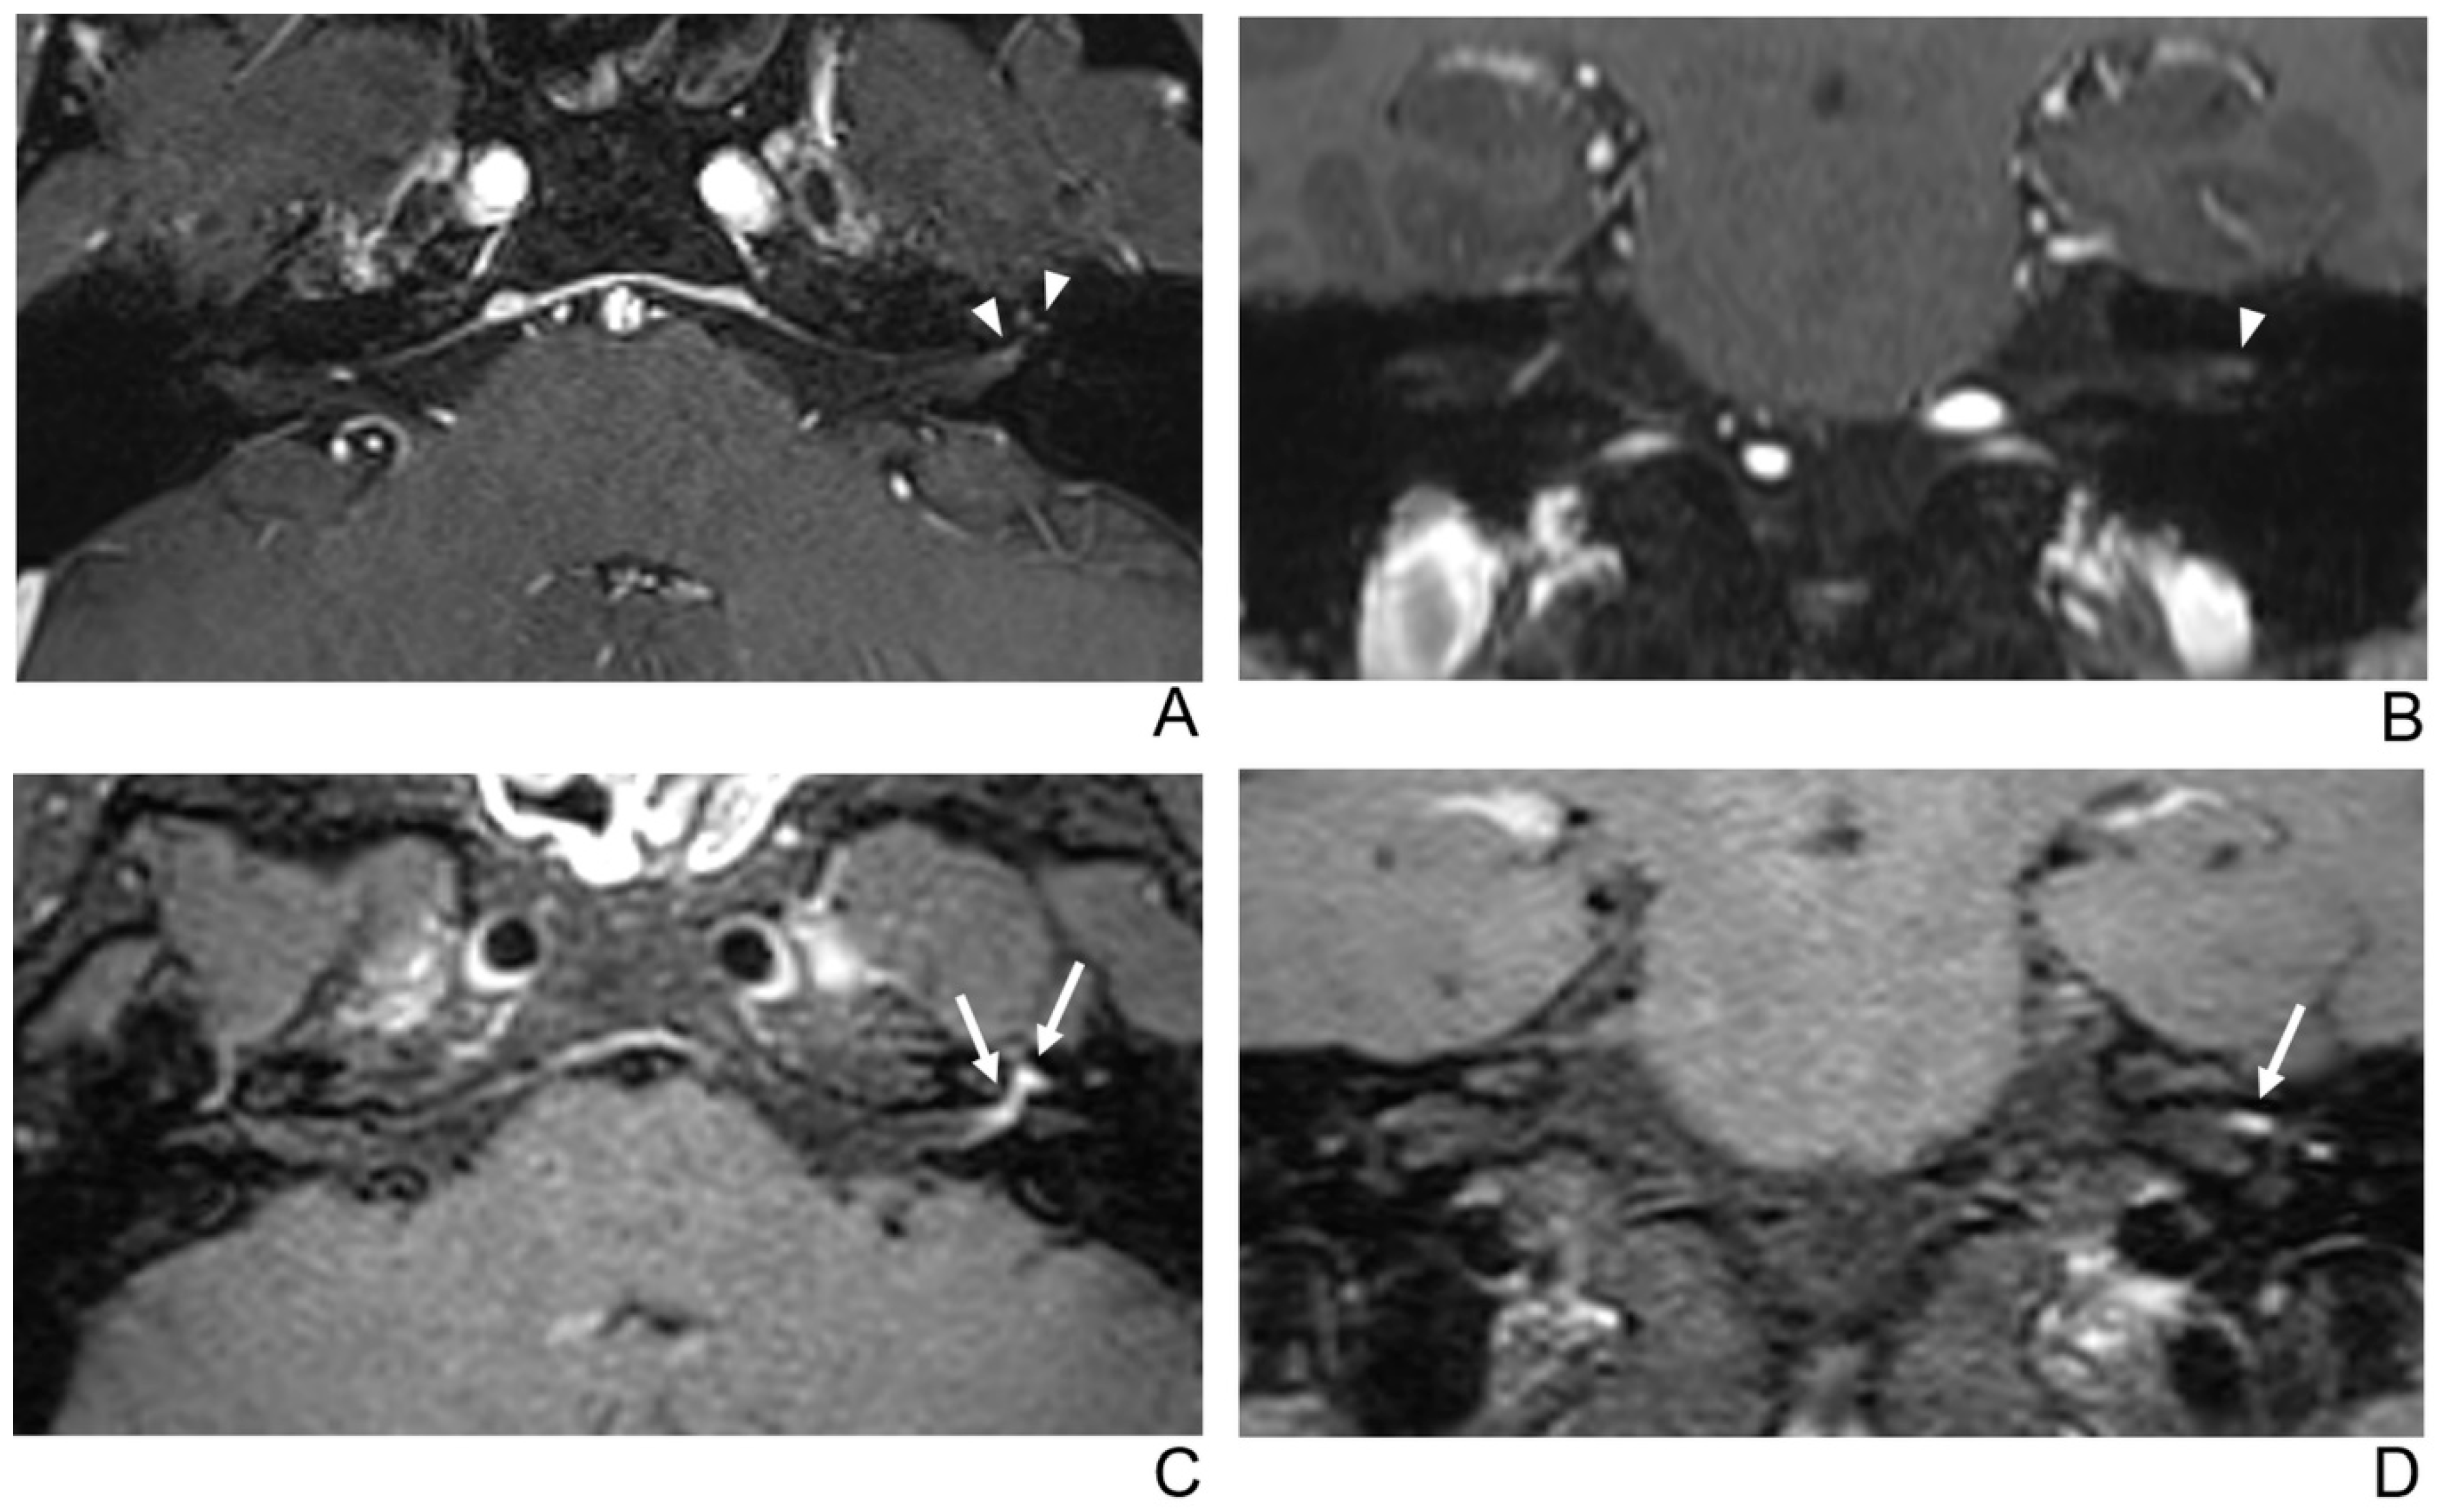

Figure 3.

A 29-year-old male patient with left facial neuritis. (A–D) Paired axial and coronal CE-GRE (A,B) and T1 BB-FSE (C,D) images of the same patient. The left distal canalicular segment of the facial nerve showed faint enhancement in the axial (A) and coronal (B) CE-GRE images (arrowheads). Those images were interpreted by reviewers 1 and 2 as suspicious left facial neuritis (1, diagnostic confidence; 1, 0, and 1, visual grades for contrast enhancement (CE) in the canalicular, labyrinthine, and anterior genu segments, respectively). In contrast, the left facial nerve shows asymmetric, intense enhancement in the canalicular, labyrinthine, and anterior genu segments in the axial (C) and coronal (D) T1 BB-FSE images (arrows); it was evaluated by reviewers 1 and 2 as left facial neuritis (2, diagnostic confidence; 3, visual grade for CE in all three segments).